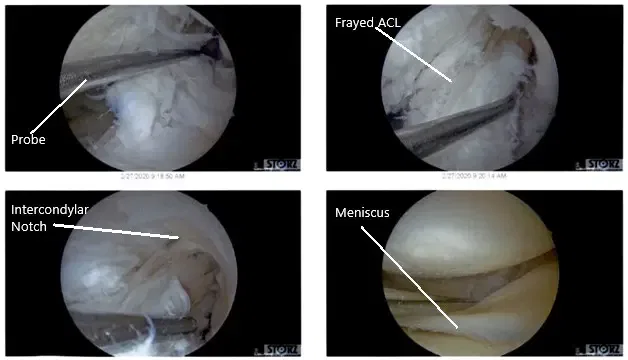

Vistas artroscópicas intraoperatorias de la rodilla izquierda.

Hubo algunos desgarros y deshilachos en el margen medial del menisco lateral, que se solucionaron con la afeitadora y la meniscectomía realizadas hasta márgenes estables. El LCA (historia de la reconstrucción del LCA) mostraba deshilachados en la muesca intertroclear, pero el LCA estaba intacto.